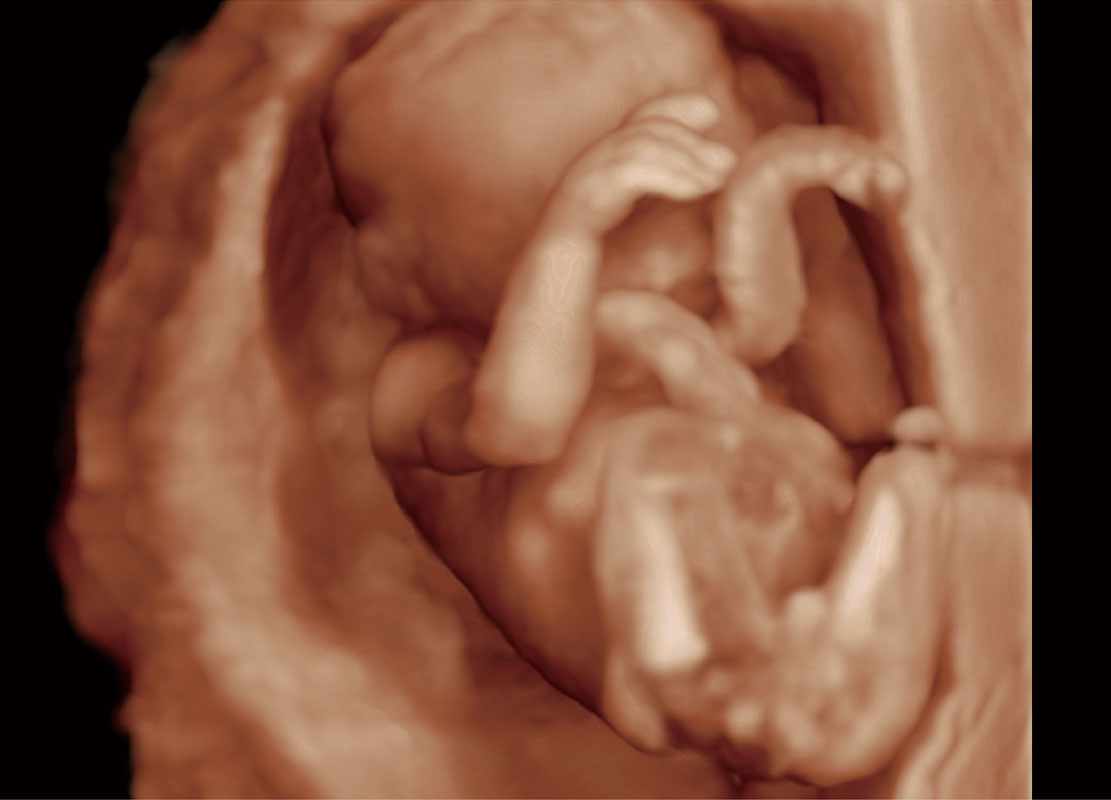

腔内三维-光影成像

光影成像-孕囊